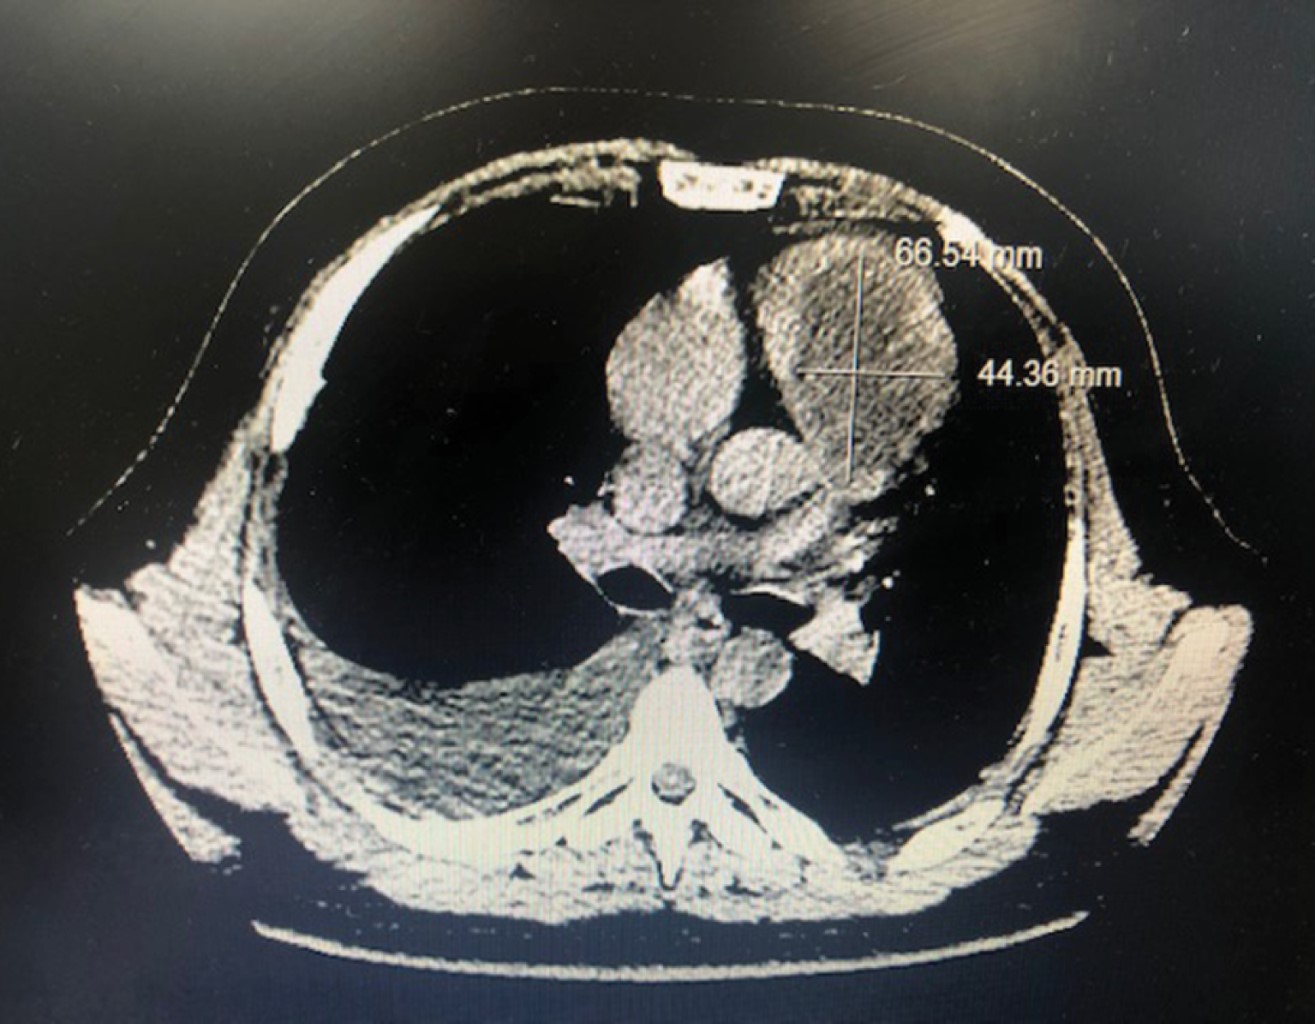

Enorme masa ventricular derecha en un paciente masculino de 25 años

Un joven varón acudió al Servicio de Urgencias del Hospital Santa Marcelina de Cidade Tiradentes con signos de insuficiencia cardíaca congestiva y pérdida de apetito. Se realizó un ecocardiograma bidimensional y se detectó una enorme masa ventricular derecha. Las masas cardíacas son siempre un desafío, y este artículo proporciona una revisión sobre el tema.

Figura 1